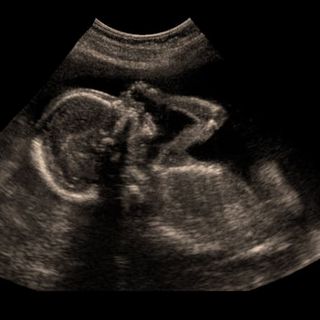

In addition to mental health issues, the researchers also looked into what happens to the fetus during pregnancy when a mother has PCOS. Specifically, they examined the neurodevelopment of children born to mothers with PCOS, finding a small but suggestive link between PCOS in women and autism spectrum disorder and attention deficit hyperactive disorder in their kids.

“The risks of a diagnosis of autism and ADHD were relatively [sic] increased, by an average of about 50%” Rees expalined, “but it’s important to recognise that the absolute numbers of children affected were still very low (<1%).”

Rees pointed to previous research that has suggested fetal exposure to higher levels of testosterone and related hormones — a characteristic of PCOS — might affect autism and ADHD risk, but that more research is needed to clarify whether and how much PCOS plays a role.

“This remains speculation at this stage and we cannot prove a causal link,” he said.